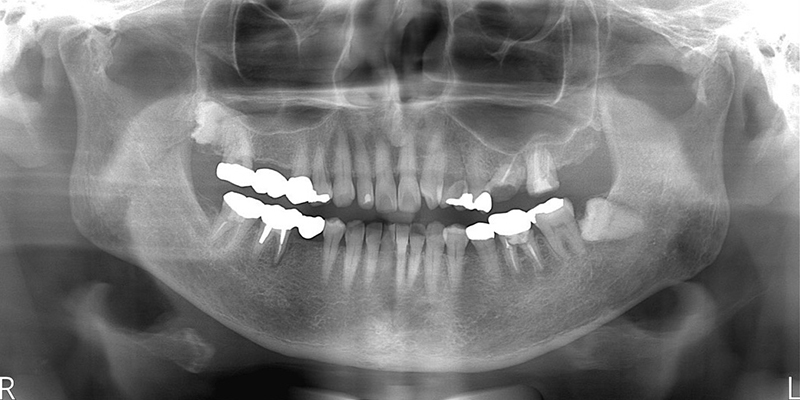

| 主訴 | ブリッジ脱離、しっかり噛めない |

| 診査診断 | 上顎歯牙欠損、歯周病、不良補綴、根尖性周囲炎。 不正咬合により噛み合わせのバランスが悪い事が原因により咬合治療が必要。 |

| 治療内容 | 欠損部インプラント 不正咬合に対し不良補綴のやり直しと合わせて咬合再構築 |